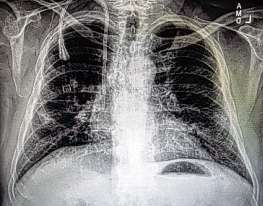

Progressive massive fibrosis occurs when dust settles in the lungs, and over time the resulting inflammation turns to hardened tissue. Medication can sometimes slow the disease’s progression, but there is no cure. Hearts fail. People can struggle to breathe as their chests fill with fluid.

Laney was skeptical, but agreed to travel to the clinic in Coal Run from his home in Morgantown, West Virginia. There, Laney viewed one X-ray after another of the worst black lung he had ever seen.

“I was sick to my stomach,” he said. “I could not believe my eyes.”